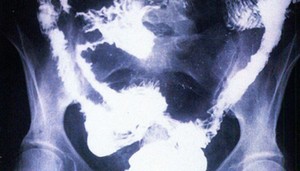

Рентгеновское исследование

1. Рентгеновский снимок живота помогает исключить осложнения, такие как перфорация или токсическое расширение толстой кишки.

2. Иригография – рентгеновское исследование с использованием двойного контраста. Признаки заболевания включают:

— сегментарное поражение кишечника

— утолщение и снижение подвижности стенок

— язвы

— рельеф кишки, напоминающий «булыжную мостовую»

— стеноз

— частичная закупорка просвета